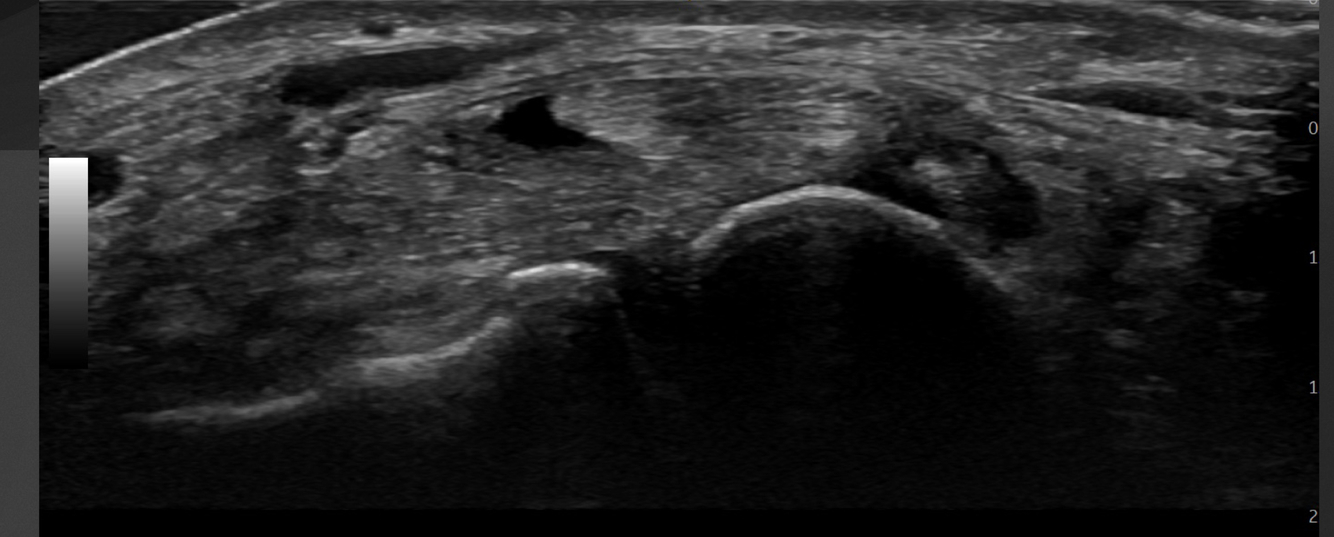

Quoi la pathologie ici?

A

Kyste ganglionnaire intra-neural (où il y a des petites étoiles